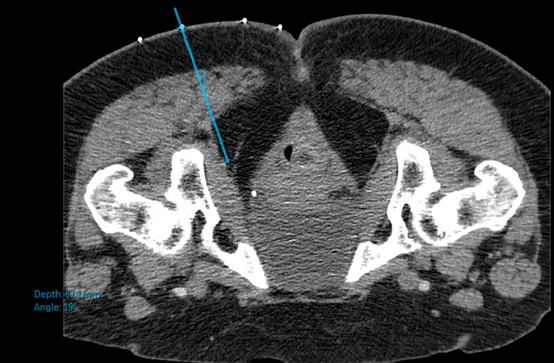

圖一:電腦斷層定位神經所在位置 (會陰神經)